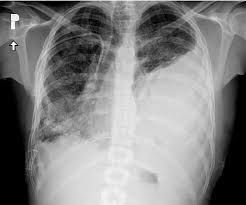

Causes of massive hemothorax

Known causes include tumour, anticoagulant therapy, arteriovenous malformation, pulmonary emboli, and tuberculosis. Tube thoracostomy drainage to evacuate unclotted blood and monitor bleeding is the first consideration in cases of haemothorax.